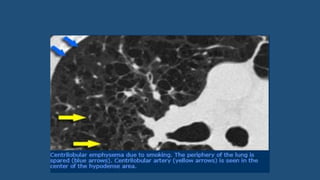

Emphysema

• Emphysema typically presents as areas of low attenuation without

visible walls.

• Centrilobular emphysema

• Most common type

• Irreversible destruction of alveolar walls in the centrilobular portion of the

lobule

• Upper lobe predominance

• Strongly associated with smoking.